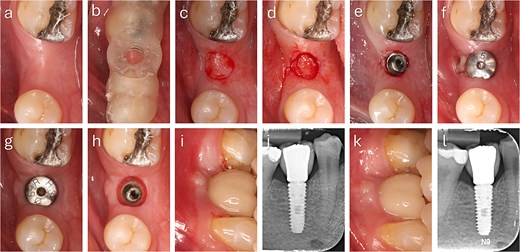

The punched graft was stabilized with corn tweezers and deepithelialized using a #15c blade (Supplementary Video S1). A buccal pouch was created with a Kirkland knife and tunnelling instruments, and the graft inserted with orientation adapted to thickness: in thin grafts (Fig. 2), the connective surface faced the implant; in thicker grafts (Fig. 3), it was oriented apically. A healing abutment coated with chlorhexidine–hyaluronic gel supported graft stabilization without sutures. A definitive crown was placed after 48 hours of implant placement in immediate loaded case.

Step-by-step clinical sequence of buccal soft tissue augmentation with deepithelialized punched tissue during delayed loading implant placement. The graft demonstrated stable integration and enhanced buccal mucosal volume at follow-up. (a) Preoperative occlusal view. (b) Surgical guide in position. (c) Exposure of keratinized tissue. (d) Removal of punched tissue. (e) Implant placement. (f) Graft positioned in buccal pouch. (g) Two-month follow-up showing improved buccal contour. (h) Mucosa after tissue former removal. (i) Final crown at two months. (j) Radiograph at two months. (k) Six-month follow-up with stable peri-implant mucosa. (l) Radiograph at six months showing marginal bone remodeling.